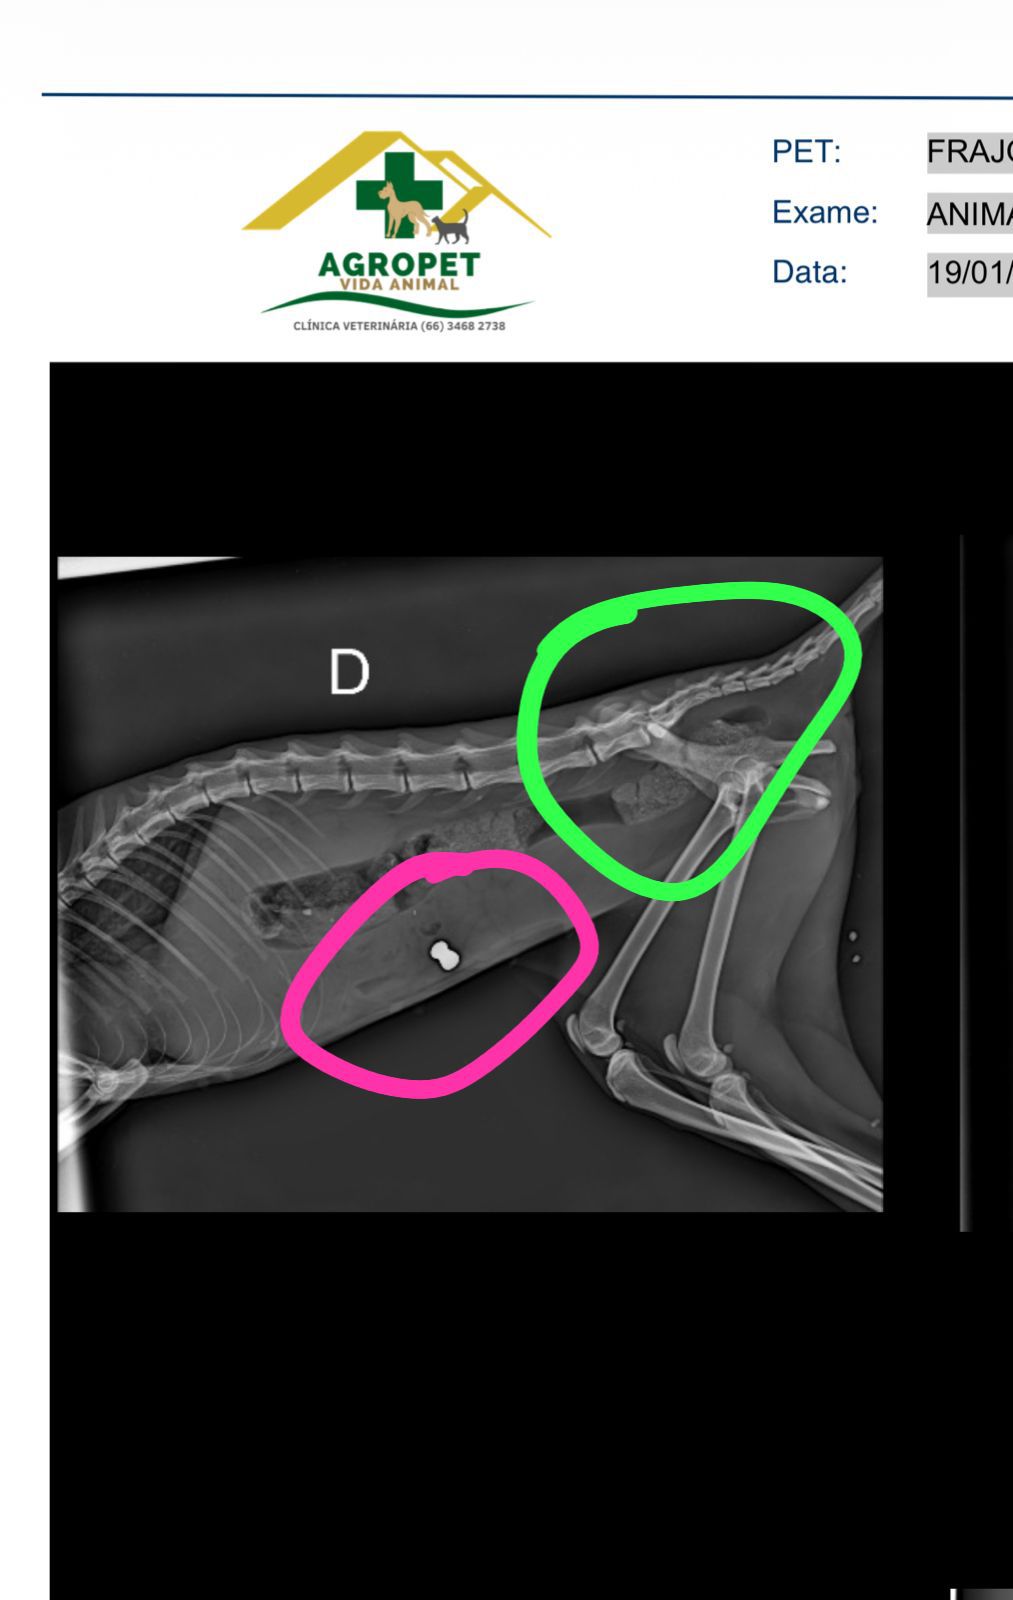

Mas o raio-x revelou algo ainda mais cruel: foi constatado um projétil alojado em seu estômago.

Agora, a Felícia luta pela vida. A mesma esta internada se recuperando e posteriormente necessita realizar duas cirurgias. (Fratura Pélvica e retirada do Projetil alojado).